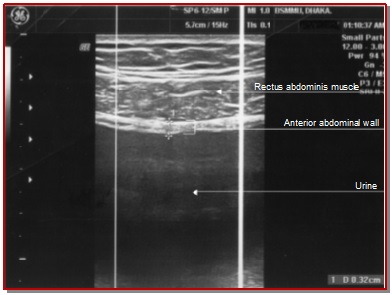

This study was performed to standardize the ultrasound estimated bladder weight as an additional non-invasive test for the measurement of the bladder outflow obstruction and to measure the therapeutic effects of bladder outflow obstruction in the follow-up after surgical correction of obstruction. This study was conducted from December 2012 to May 2014 where the sample size was 55 and sampling technique was purposive. In bladder outflow obstruction patient, transabdominal sonography was performed using a 7.5 MHz. probe. The anterior bladder wall thickness was measured in three points in the midline 1 cm apart and the average value was recorded. After that bladder volume was measured by ultrasonogram. In pre- and post-operative groups ultrasound estimated bladder weight was measured from bladder wall thickness and bladder volume. In this study, the mean ± SD of age was 48.8 ± 15.0 years. In bladder outflow obstruction patient, the pre-operative ultrasound estimated bladder weight was 117 ± 45.1 g which was reduced to 53.9 ± 10.8 g three months after surgical correction of obstruction. The ultrasound estimated bladder weight is a non-invasive, cheap and easily available additional diagnostic tool for detecting bladder outflow obstruction as well as it can measure the therapeutic effects in post-operative period.